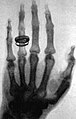

Am 8. November 1895 entdeckte Wilhelm Conrad Röntgen in Würzburg die unsichtbaren Strahlen. Er experimentierte mit einer fast luftleeren Kathodenstrahlröhre aus Glas. Er deckte sie mit Pappe ab, aber die Strahlen konnten sie durchdringen und zeigten ein zufällig auf dem Tisch liegendes Objekt auf dem Fluoreszenzschirm.[1][2] Am 28. Dezember übergab er seine erste schriftliche Mitteilung „Über eine neue Art von Strahlen“ der Physikalisch-Medizinischen Gesellschaft zu Würzburg und am 23. Januar 1896 kam es zur ersten öffentlichen Demonstration seiner Entdeckung.[3][4] Er verzichtete auf eine Patentierung, damit die Röntgenapparate schneller eingesetzt werden konnten.[5] Für seine ab 1896/1897[6] weltweit genutzte Entdeckung erhielt Röntgen 1901 den ersten Nobelpreis für Physik. Ausgehend von Röntgens Entdeckung entwickelte Carl Heinrich Florenz Müller gemeinsam mit Ärzten die erste wassergekühlte Anode.

Historische Aufnahme einer Hand mit Ring (Röntgen, 23. Januar 1896) -